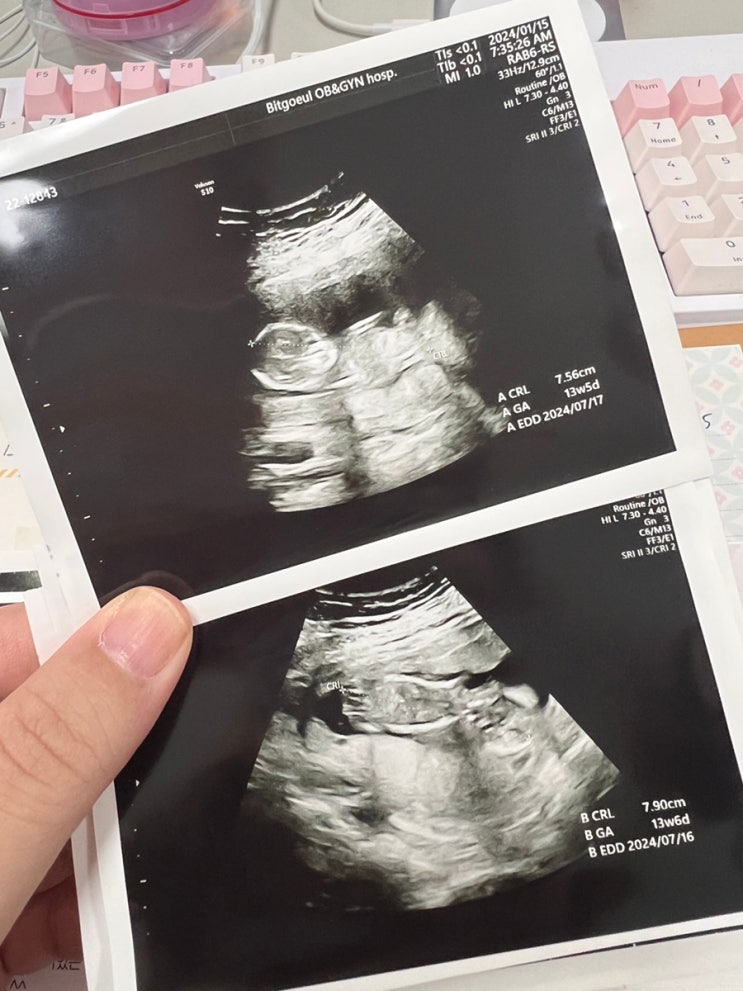

임신 11주-13주0일까지 일상/끝나지않는 입덧, 갈색혈

또 몰아쓰는일기 왜냐... 어디도 못가는중이라 쓸 일상이 없댜... 10주 주말 이날이 성탄절 직전이라 친정...